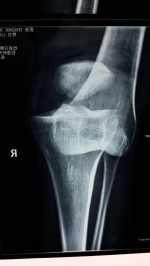

左脛骨近端骨折后外側(cè)塌陷病例一例分享 關(guān)鍵疾病:左脛骨近端粉碎性骨折,左膝內(nèi)外側(cè)半月板損傷,左膝前后交叉韌帶損傷,左膝關(guān)節(jié)腔積液 現(xiàn)病史【一般資料】 女性,64歲,農(nóng)民 【主訴】 摔傷后致左膝關(guān)節(jié)腫痛,活動(dòng)受限2小時(shí)。 【現(xiàn)病史】患者訴2小時(shí)前在家中干活時(shí)不慎摔倒,傷及左膝部,當(dāng)即感左膝關(guān)節(jié)疼痛明顯,腫脹,不能站立及行走,傷時(shí)無(wú)昏迷及逆行性遺忘,遂急來(lái)我院就診,急診X線檢測(cè)示左脛骨近段骨折,為求進(jìn)一步系統(tǒng)治療,急診以“左脛骨近端骨折”收住院。病程中,患者訴左膝腫痛重,無(wú)頭暈頭痛,無(wú)胸悶憋喘,二便未解,納飲未行。 【既往史】患者平素體??;否認(rèn)高血壓、糖尿病、冠心病病史,否認(rèn)肝炎、結(jié)核等傳染病史,否認(rèn)手術(shù)及輸血史,否認(rèn)食物和藥物...